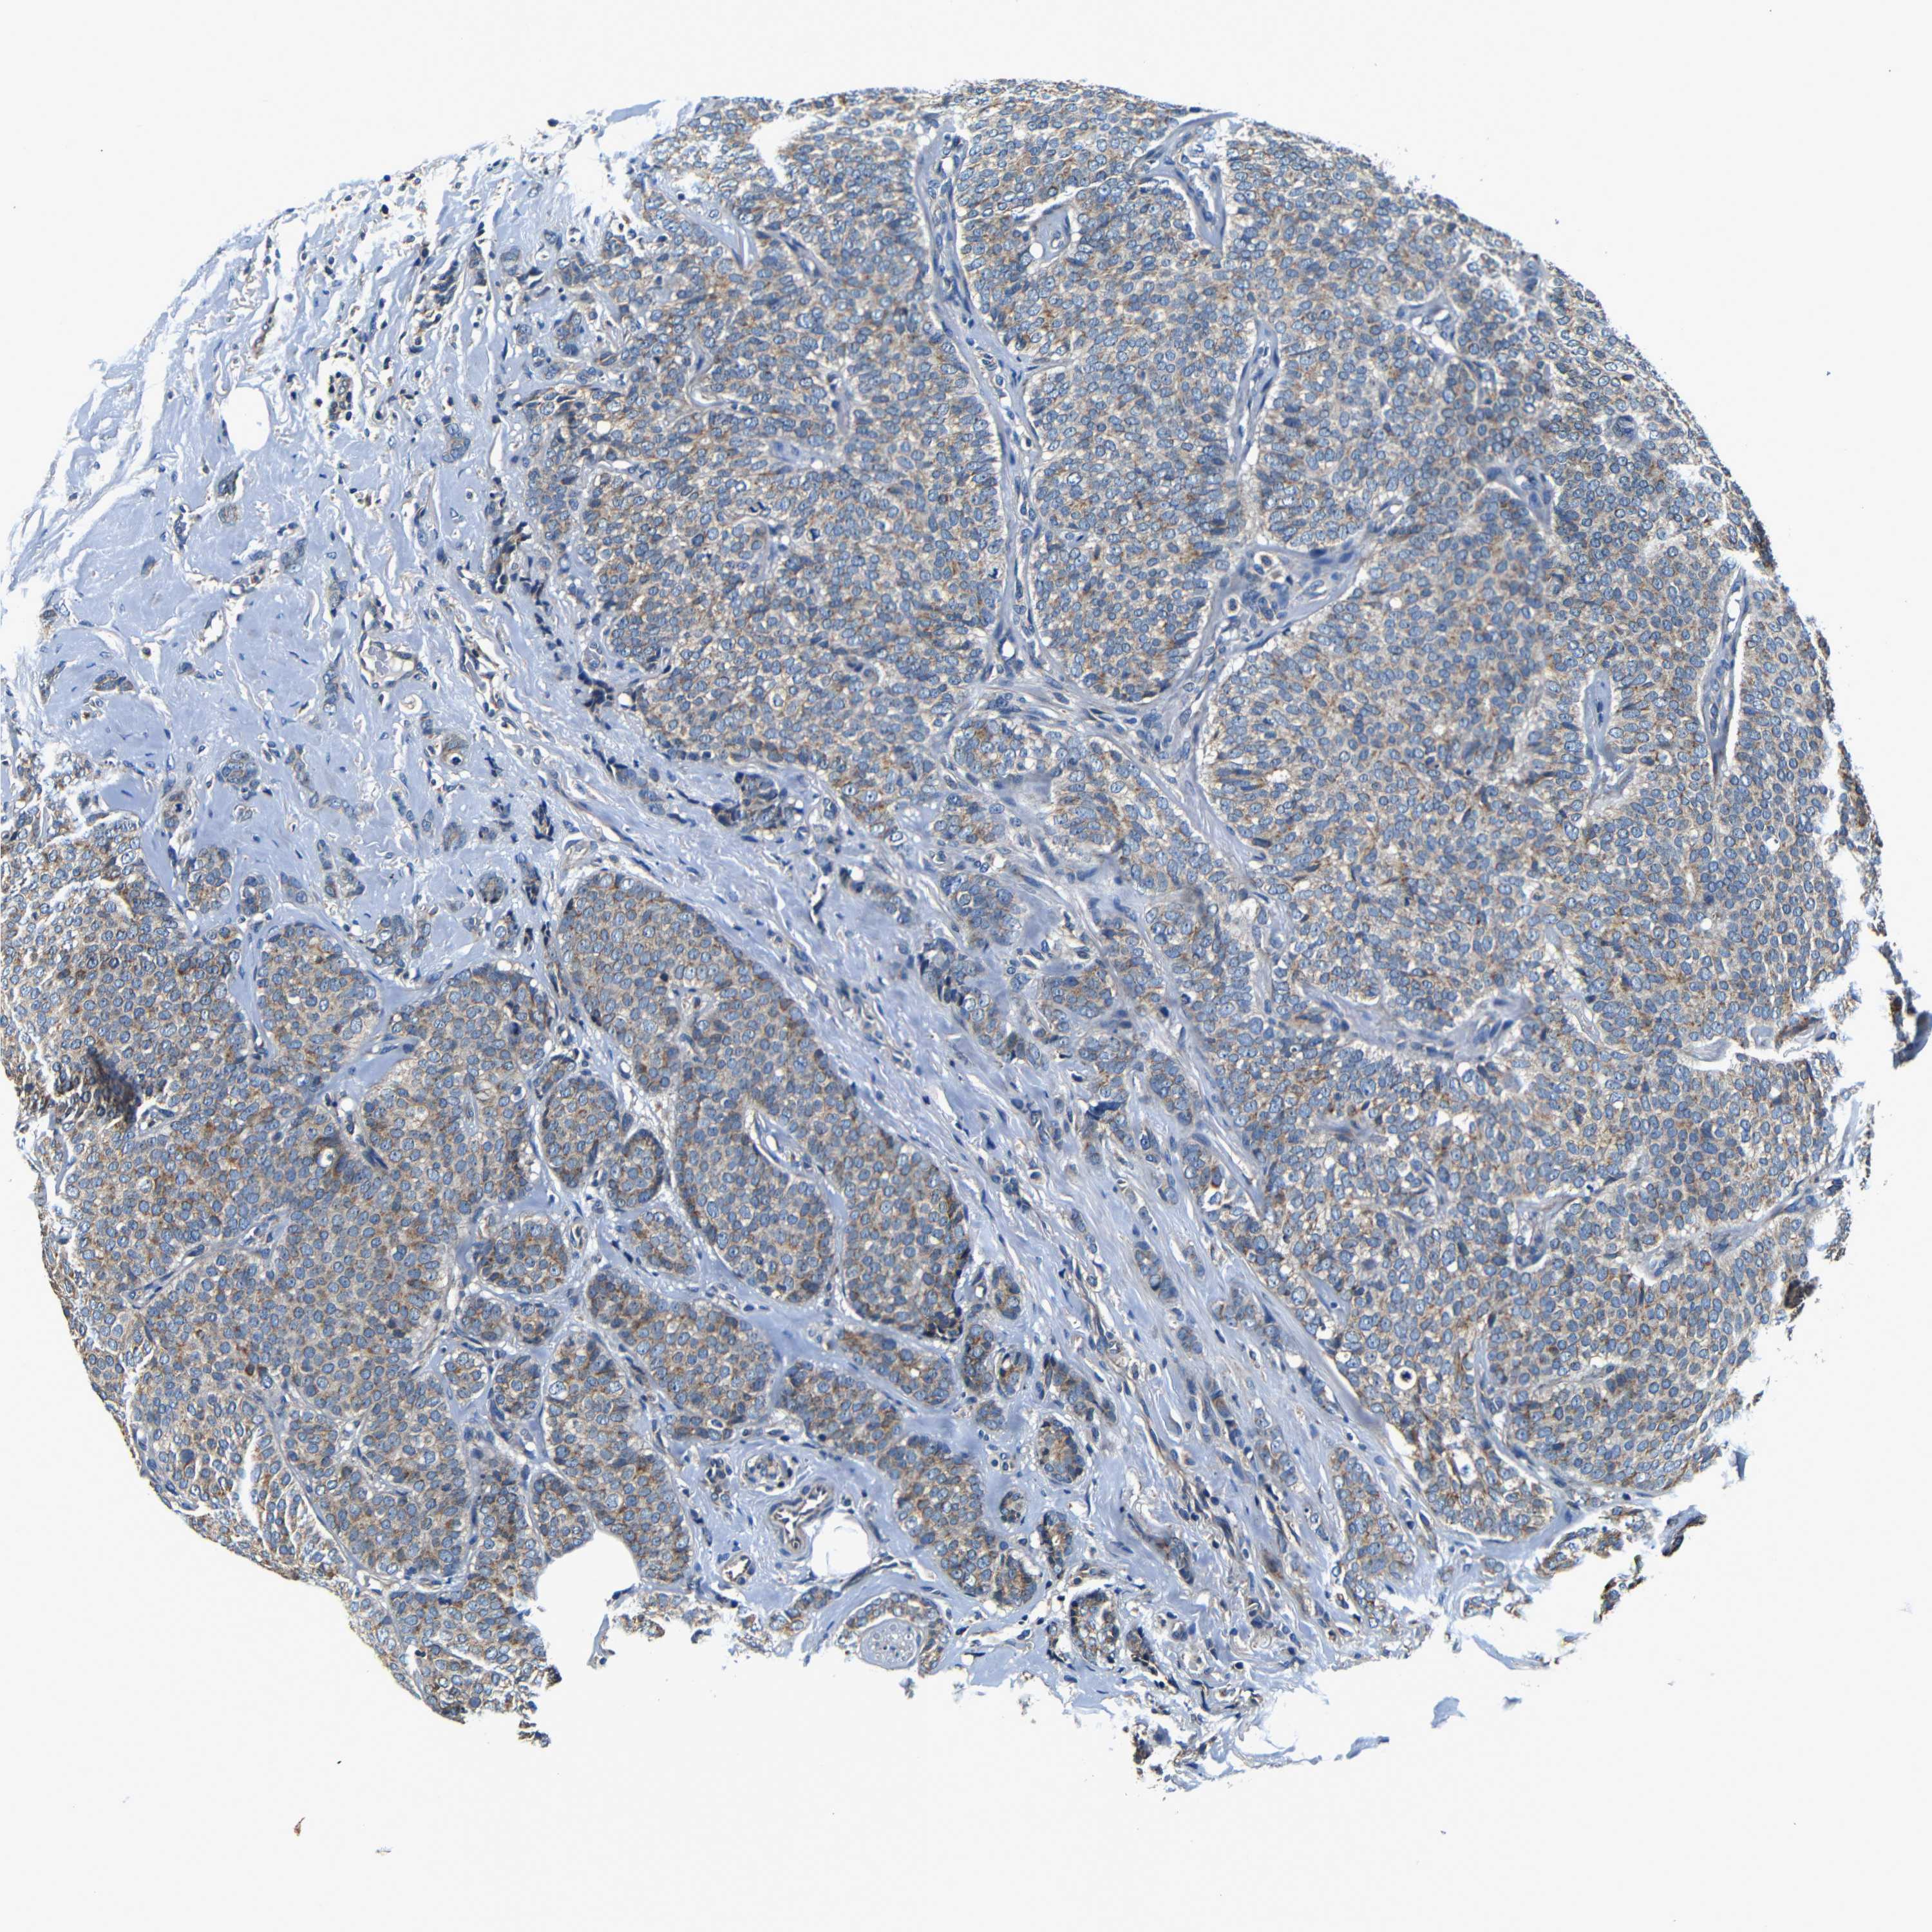

CANCER BREAST CANCER Show tissue menu

BRCA TCGA BRCA VALIDATION PROTEIN EXPRESSION

Breast cancer

Human cancer